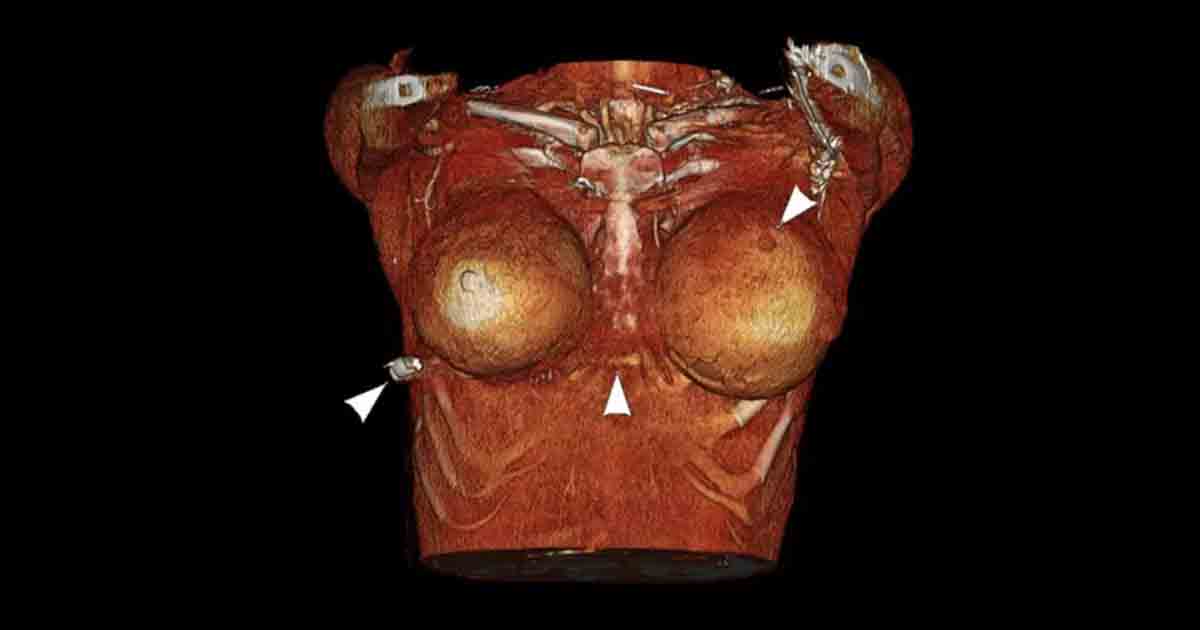

“The bullet wound entry was on the left breast, but the rib fracture was on the right side. The bullet entered the skin on the left side first, and then ricocheted across her sternum into the right breast and broke her rib on the right side,”

“The implant caused the change in the trajectory of the bullet,”

As the operation goes, medics found a hard, bullet-like object in the woman’s right lower anterior thoracic wall below the right breast.

Using trauma radiographs, medical experts were able to find the bullet in the right lateral thoracic wall, a fractured rib and air bubbles in the left breast, and concluded that the bullet traveled from the left breast to the right thoracic wall.